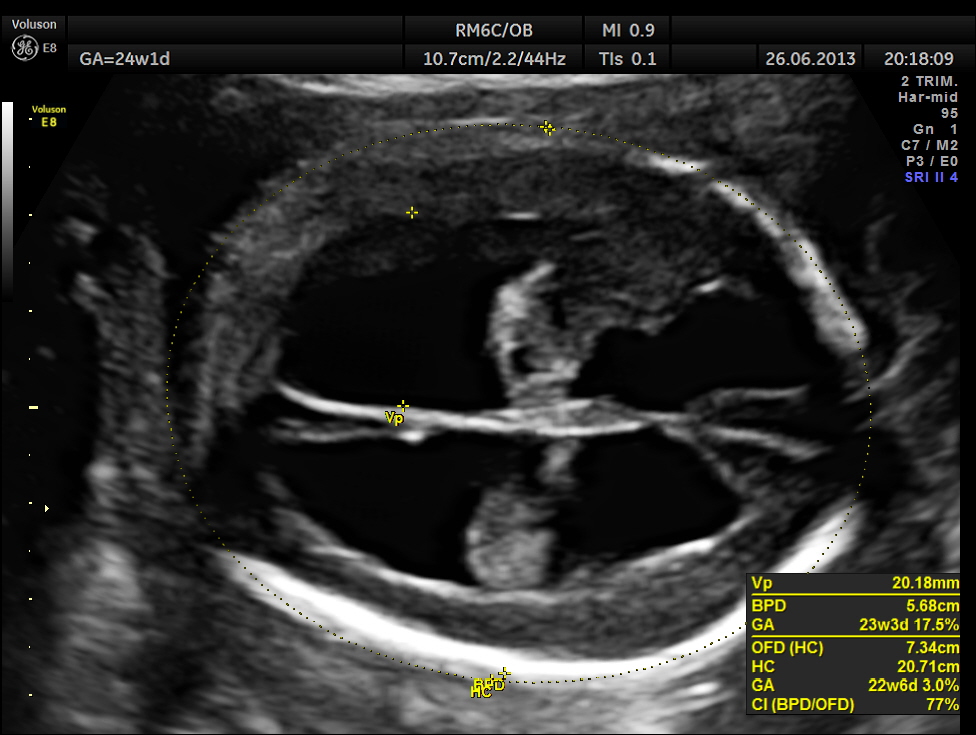

This was a 24 year old lady referred for 2 nd opinion for hydrocephalus.

Hydrocephalus was confirmed.

The cerebellum was distorted in shape – boomerang shaped and the cisterna magna was almost obliterated.